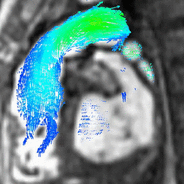

Blood flow and physiology

Blood flow can be visualized and quantified on scans acquired with a scan sequence called 4D flow. These volumetric scans capture multidirectional flow values anywhere within the imaged volume throughout the cardiac cycle, leading to a comprehensive exam of the entire anatomy.[15] Visualization can display flow velocity maps, vectors and streamline

4D flow visualization. flow (left) and streamlines (center) and vectors (right).